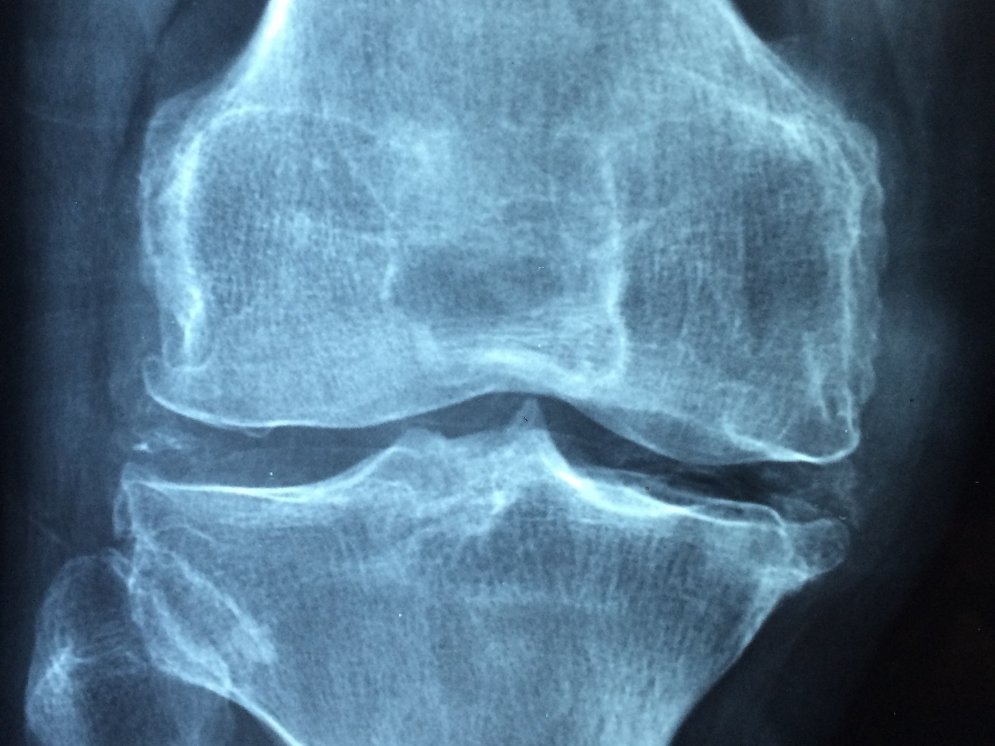

Chondroitin verbessert die Aufnahme von Wasser in die Knorpelmasse des Gelenkes. Dieses wirkt dann zusammen mit körpereigenen Stoffen wie ein Schmiermittel. Altersbedingt kann zu wenig Chondroitinsulfat vorhanden sein bzw. kann aufgrund von starker Abnützung des Gelenkes Chondroitinsulfat aus der Knorpelmasse verdrängt werden. Chondroitinsulfat wirkt außerdem schmerzlindernd und entzündungshemmend. Wie diese Wirkung zu erklären ist, steht noch nicht eindeutig fest. Diskutiert werden u. a. eine Hemmung diverser Enzyme und die Inaktivierung reaktiver Sauerstoff-Radikale. Chondroitin wird meist aus Haifischknorpel hergestellt. Da man nun weiß, dass sich beschädigter Knorpel auch regenerieren kann, ist Chondrotin ein wichtes Mittel zur Vorbeugung und Behandlung von Arthrosen.Voraussetzung ist allerdings der frühzeitige Beginn – völlig zerstörter Knorpel kann nicht wieder hergestellt werden. Chondroitin bewirkt auch, dass mehr Hyaluronsäure in die Gelenke aufgenommen wird. Die Hyaluronsäure ist ebenfalls ein wichtiges „Schmiermittel“.